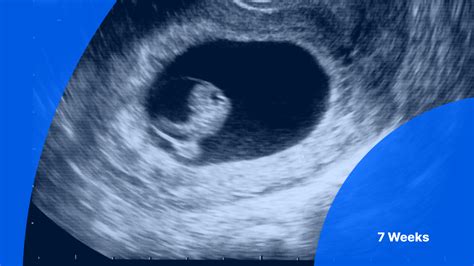

A 7 week ultrasound is a critical milestone in pregnancy, offering a wealth of information about the developing fetus. At this stage, the embryo has undergone significant growth and development, and various structures can be visualized using high-frequency ultrasound. This examination is typically performed transvaginally, providing a more detailed view of the embryo and its surroundings.

During a 7 week ultrasound, the sonographer or healthcare provider will assess several key aspects of fetal development. The embryo's size, measured from crown to rump, is usually around 10-12 millimeters in length. The heart rate can be detected, and its rhythm and frequency are evaluated to ensure they fall within normal ranges. The presence of a yolk sac, which provides nutrients to the embryo before the placenta takes over, is also confirmed. Additionally, the sonographer may identify the beginnings of limb buds, which will eventually develop into arms and legs.

- Limb buds, which will develop into arms and legs, may be visible, although their definition is still limited.

- Transvaginal ultrasound provides a clearer view of the embryo and its surroundings compared to transabdominal ultrasound at this gestational age.